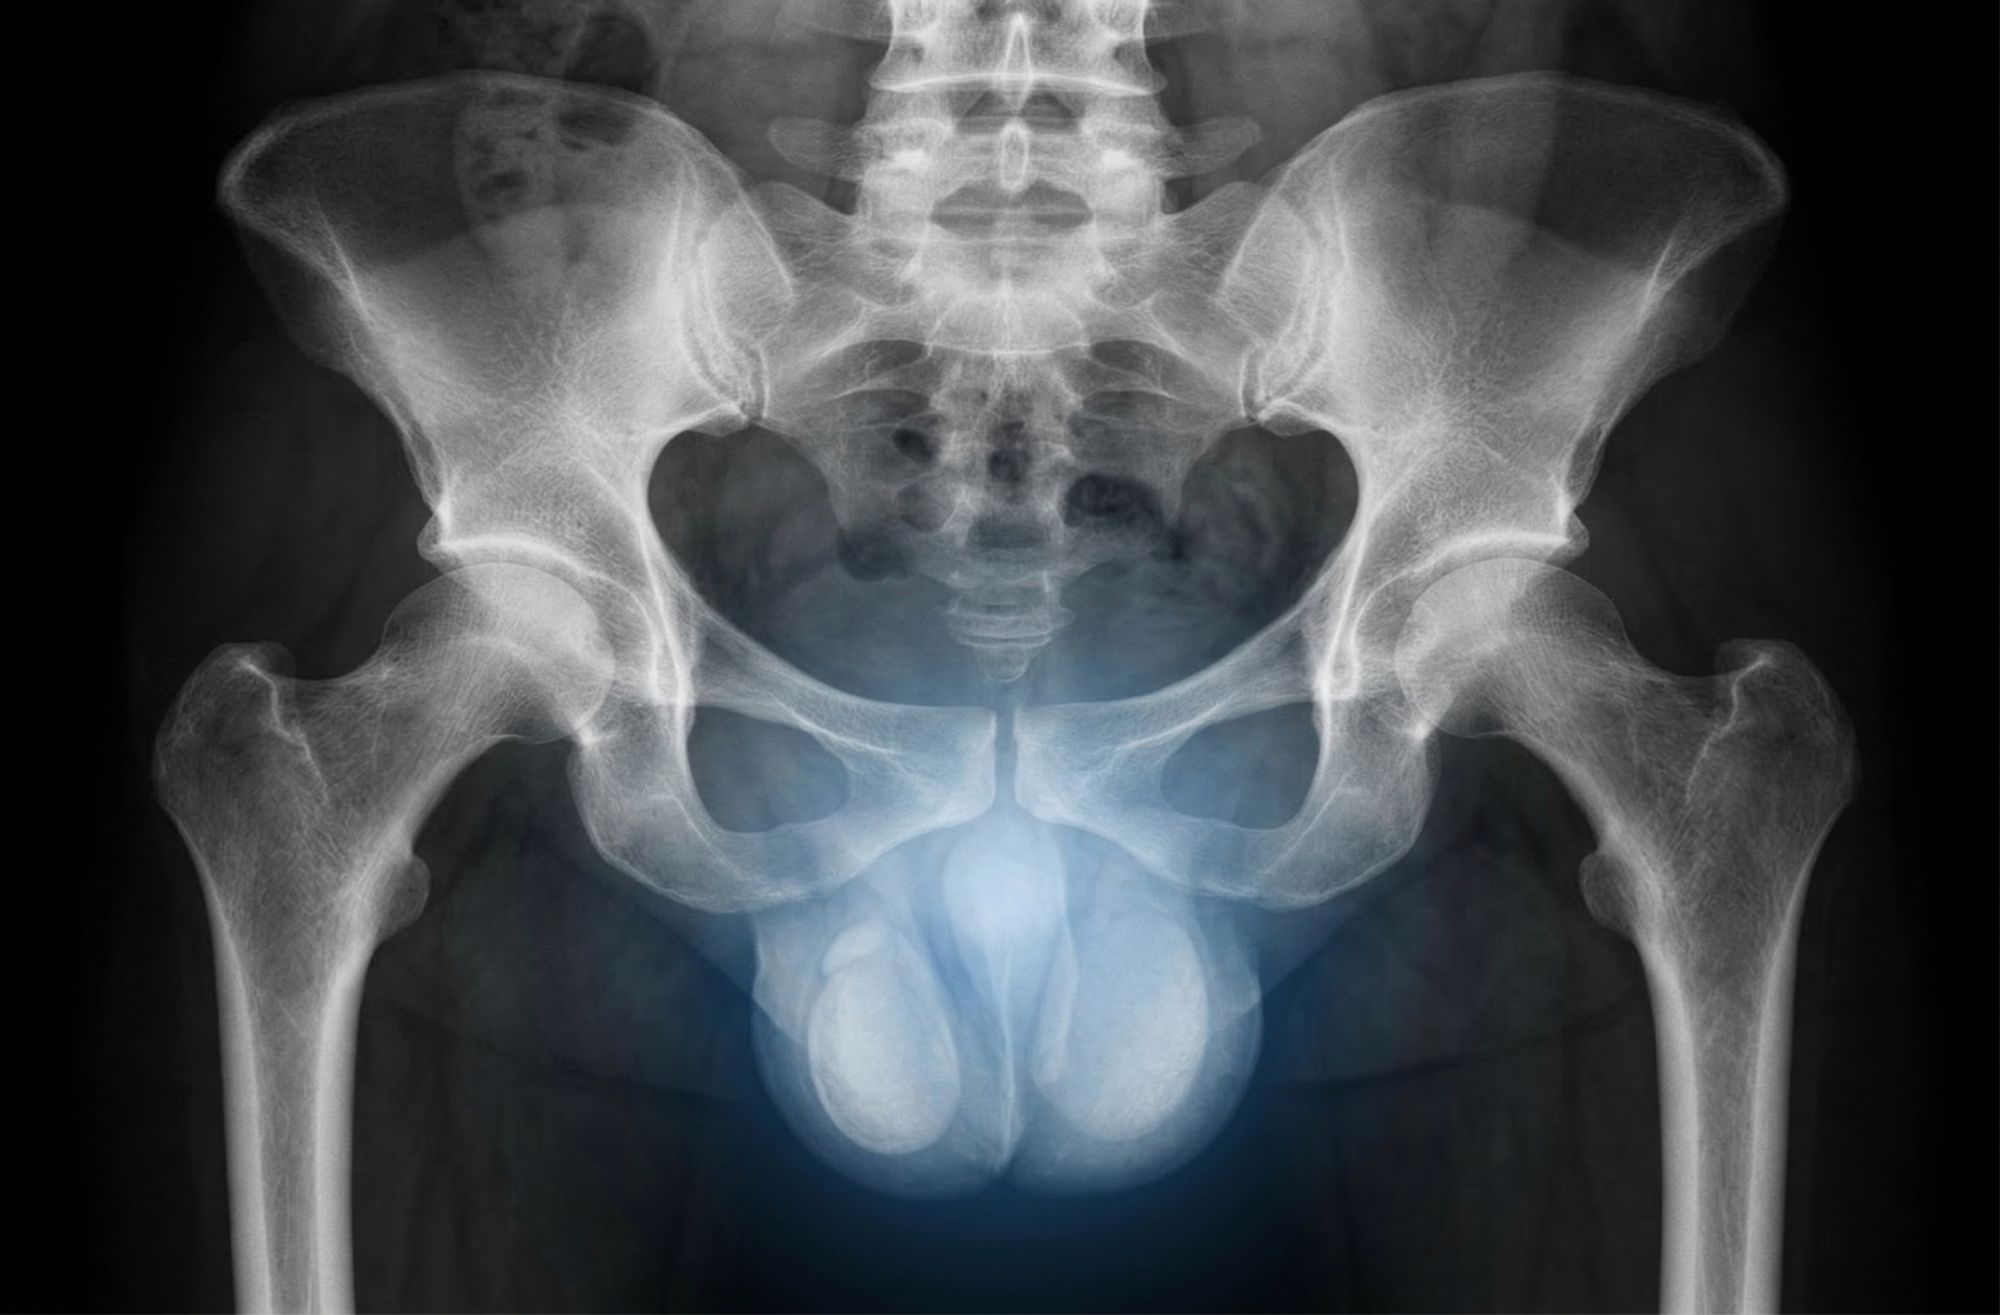

УЗИ мошонки у мальчиков: о чем молчат подростки и что должны знать мамы

Ультразвуковое исследование яичек (диагностика варикоцеле) на аппарате экспертного класса.

Здоровье будущего мужчины закладывается в раннем детстве, но тема мужской половой сферы часто остается «неудобной». Мальчики стесняются жаловаться на дискомфорт, а мамы боятся задать лишний вопрос. Рассказываем, зачем делают УЗИ органов мошонки, как вовремя распознать варикоцеле у подростков и почему при перекруте яичка счет идет на часы.

Варикоцеле у подростков: скрытая угроза будущему отцовству

Период активного роста (12–15 лет) — время, когда у мальчиков может развиться варикоцеле (расширение вен семенного канатика). Коварство этого состояния в том, что оно редко болит. Ребенок может чувствовать лишь легкую тяжесть после физкультуры, которой не придаст значения.

Почему это важно? Расширенные вены повышают температуру внутри мошонки, что губительно для клеток, отвечающих за детородную функцию. УЗИ с допплерографией позволяет выявить варикоцеле на самых ранних стадиях, когда проблему можно решить бережно, сохранив мужское здоровье на всю жизнь.

Перекрут яичка: когда счет идет на часы

Это критическое состояние, о котором должен знать каждый родитель мальчика. При перекруте яичко поворачивается вокруг своей оси, перекрывая кровоток.

Немедленно обратитесь к врачу, если ребенок жалуется на:

• Резкую, сильную боль в мошонке или внизу живота.

• Быстро нарастающий отек и покраснение.

• Тошноту и рвоту на фоне боли.

В этой ситуации УЗИ помогает врачу мгновенно оценить состояние кровотока и принять решение о спасении органа. Помните: при перекруте помощь должна быть оказана в первые несколько часов.